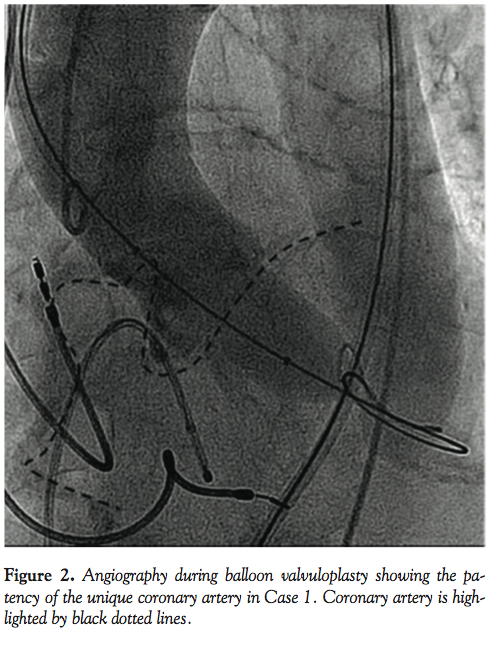

This particular anatomy was therefore not considered a contraindication to the TAVI procedure because the coronary ostium was far enough from the aortic annulus and the sinuses of Valsalva were large enough to accommodate the TAVI prosthesis without compromising the single coronary artery origin. Prior to the implantation of a 23 mm Edwards SAPIEN XT valve, a valvuloplasty was performed (23 mm balloon) with concomitant aortography, confirming the patency of the coronary artery (Figure 2). TAVI was successfully carried out without any coronary obstruction or significant paravalvular leakage. On day 2, MSCT was obtained; the prosthesis was correctly positioned, without obstruction of the coronary artery (Figure 3). At 12-months follow-up exam, the patient was in NYHA II class, without any clinical events.

The risk of coronary obstruction and subsequent death is intuitively high in this group of patients. The main risk is an obstruction of the unique coronary artery by a bulky calcified leaflet. In our cases, the risk of any external compression of the abnormal LCA, in its retro-aortic course, seems very low. Indeed, it is unlikely that the anomalous vessel would be compressed against any fixed structure in taking this course, since no portion of the single artery appears intramural. Moreover, there does not appear to be a split-like origin to either the RCA or the origin of the LCA from the right sinus of Valsalva. The anticipation of such a life-threatening complication relies on the appropriate sizing of the annulus and an appreciation of the relative distance from the aortic annulus to the coronary ostium. The precise analysis of the dimensions of the sinuses of Valsalva is also paramount; sinuses should be wide and high enough to decrease the risk of coronary occlusion either by a bulky calcified leaflet or the frame of the prosthesis. MSCT is the tool of choice to analyze these parameters and precisely define the coronary arterial anatomy and its course. Angiography during balloon valvuloplasty is also of major importance to anticipate any risk of coronary obstruction prior to valve insertion. The balloon-annulus ratio should be close to 1. This technique is routinely applied in our institution for all TAVIs, since it provides three types of information: further appreciation of the annulus diameter; estimation of the risk of coronary obstruction; and anticipation of valve embolization, particularly in cases of implantation of the SAPIEN XT device in patients with severe septal hypertrophy. The appropriate valve-annulus ratio has to be defined for each patient prior to the procedure; a 1/1 ratio seems reasonable. Indeed, the oversizing of the prosthesis should be minimized to avoid coronary compression.